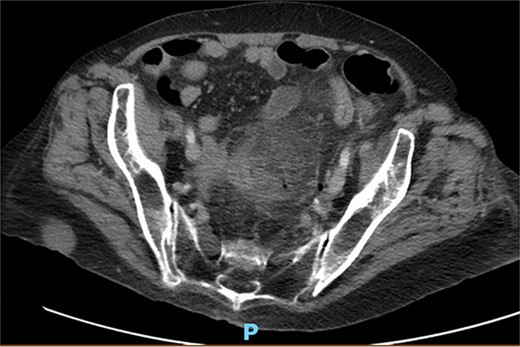

A 65-year-old female with a history of hyperlipidemia, hypertension, hip replacement, lumbar spinal fusion, chronic pain management, and prior laparotomy for endometriosis presented with a 3-day history of nausea, vomiting, and abdominal pain. She had no prior history of diverticulosis or colonoscopy. On examination, she was afebrile and hemodynamically stable. Physical examination revealed left lower quadrant tenderness, swelling, erythema, and fluctuance, suggesting an abdominal wall abscess (Figs 1 and 2). Laboratory tests showed leukocytosis with a count of 24.6 and a positive urinalysis with 2+ leukocytes. A CT scan of the abdomen and pelvis revealed a 3.8 × 3.6 cm air and fluid pocket in the low left anterior abdominal wall, indicative of an abscess likely at the site of a previous drain (Fig. 3). Additionally, there was a 2.8 × 1.8 cm irregular air pocket in the left pelvis, where an abscess had been identified in prior imaging.

CT from readmission with anterior abdominal wall abscess and left pelvic abscess.

One month prior, the patient was admitted for complicated perforated sigmoid diverticulitis. Treatment included piperacillin-tazobactam (Zosyn), bowel rest, and fluid resuscitation. On hospital Day 6, her condition worsened with increased nausea, vomiting, and an elevated WBC count of 15. CT imaging revealed a 4.8 × 4.4 × 4.0 cm diverticular abscess, leading to CT-guided percutaneous drainage by interventional radiology (Figs 4–7). Cultures grew Citrobacter sedlakii and Enterococcus faecium vancomycin resistant Enteroccus (VRE), and treatment was adjusted to include Bactrim, followed by daptomycin and levofloxacin. The abscess resolved after 3 weeks, and the drain was removed before discharge. The patient was instructed to follow up with her surgeon and undergo a 6-week interval colonoscopy.